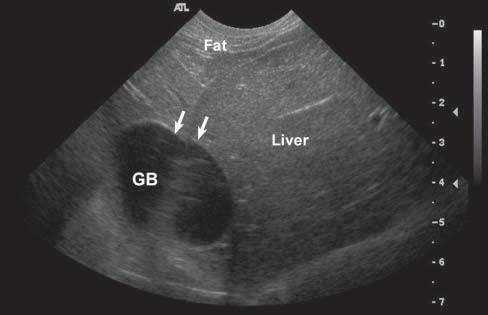

SpeedErrorandRangeAmbiguity Artifacts

Whentheultrasoundspeedisnottheassumed 1,540m/sthroughtissues,errorsinsizeorlocation ofstructuresmayarise(Feldmanetal.2009;Hindi etal.2013).Forexample,whensoundtravelsthrough fat(withavelocityofabout1,450m/s),thereturning echoeswilltakelongertocomebacktothetransducer andthusbedisplayeddeeperintheimagethanthey reallyare(Figure1.20). Speed–orpropagation–error artifactsmaycausestructurestobeinaccurately localizedormeasured.

Figure1.20. Speederror. Whensoundtravelsthroughfat (withavelocityofabout1,450m/s),thereturningechoestake longertocomebacktothetransducerandarethusdisplayed deeperintheimagethantheyreallyare.Inthisnormaldog, theslowervelocityofultrasoundwavesthroughfatincomparisontoliver(around1,600m/s)resultsininaccuratedisplacementoftheGBfurtherawayfromthetransducer.